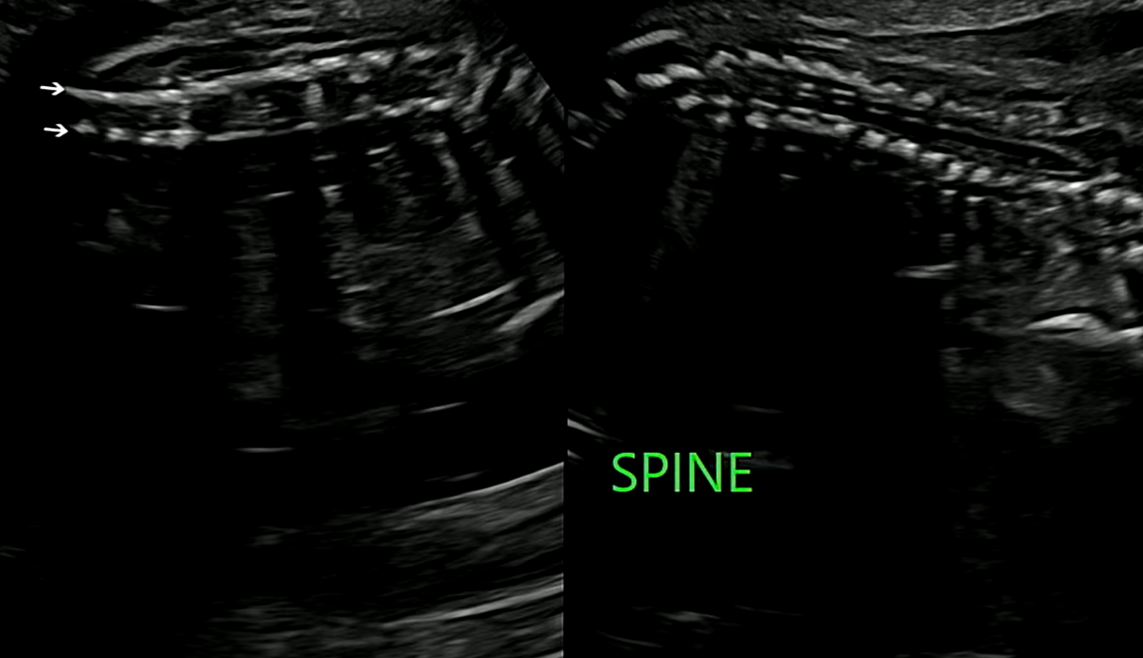

척추

척추도 잘 크고 있는 것을 초음파를 통해 볼 수 있었다.